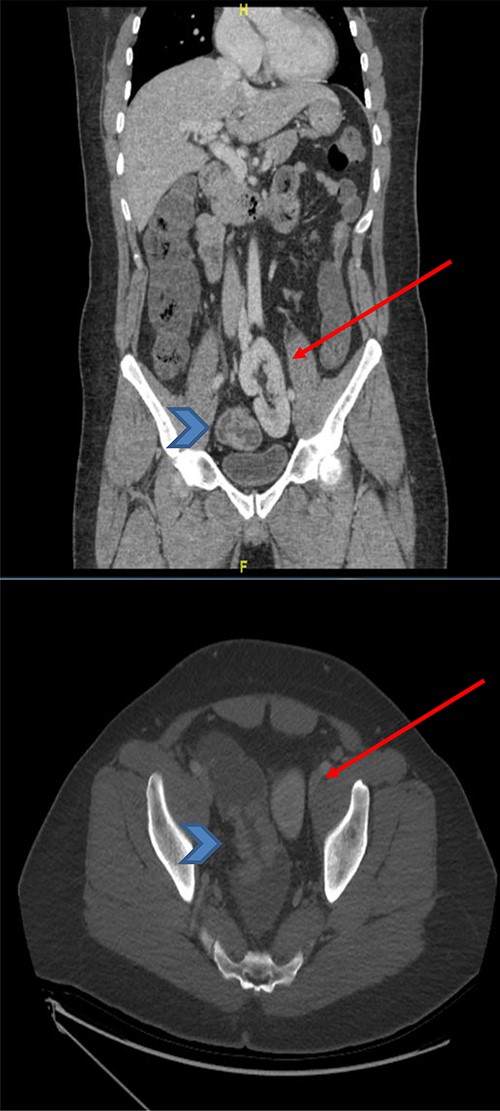

The basic lab Investigation showed Hgb level of 8.6 g/dL and CEA level of 4.8 ng/ml. On further investigation, colonoscopy revealed a large friable fungating circumferential rectal mass at 9 cm from anal verge extending to the distal sigmoid colon, it was nonobstructing with a length of 8 cm and the rest of the colon was normal. A biopsy from the mass was taken and showed invasive moderately differentiated adenocarcinoma. On further routine of radiological staging, CT of the chest, abdomen and pelvis confirmed the upper rectal mass with ectopic malrotated left kidney located in the lower abdomen and upper pelvis, opposite to L5-S1 vertebral bodies (Figs 1 and 2). There was no peritoneal disease or distant metastasis. Moreover, MRI pelvis showed again an upper rectal mass with mesorectal fat invasion and multiple lymph nodes (T3N2) and confirmed an ectopic left kidney (Figs 3 and 4).

CT scan of the abdomen and pelvis (coronal and axial view) showing the upper rectal mass (arrowhead) with ectopic kidney (arrow), clear plane noted in-between without tumor invasion.